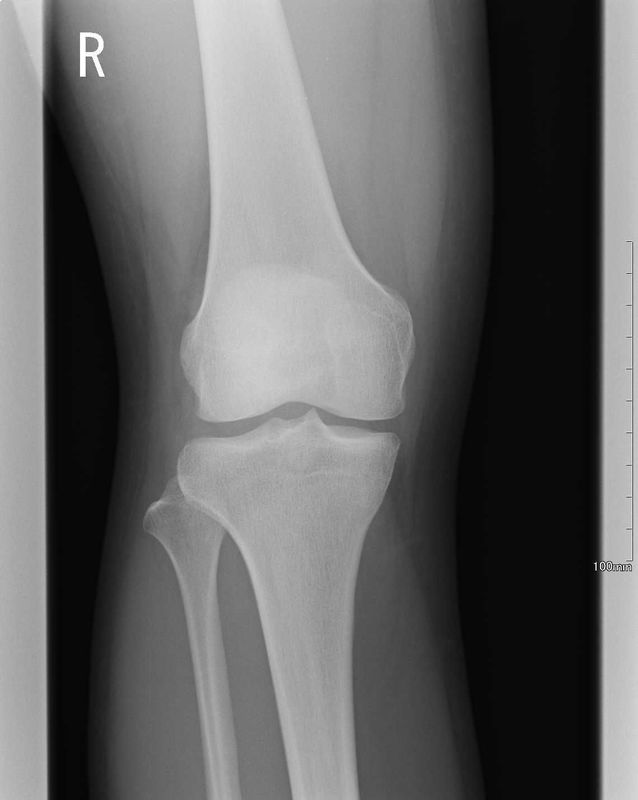

術前画像

| レントゲン | MRI |

| 骨傷なし、関節変形なし | ACLの連続性や緊張がみられない |